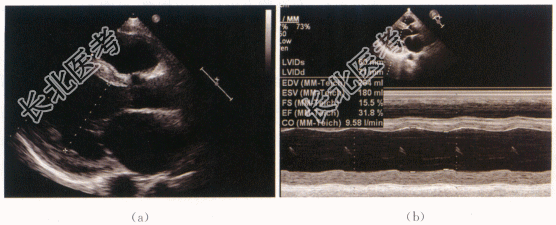

- [材料题] 患者,男性,29岁,因“双下肢水肿1周”就诊。患者1周前开始无明显诱因下出现双下肢凹陷性水肿,病情逐渐加重,先后出现双大腿、阴囊水肿、腹腔积液及胸腔积液,入院前一周出现咳嗽,夜间不能平卧。既往否认高血压、糖尿病等慢性病史。体格检查:患者慢性病容,胸廓外型正常,双侧呼吸运动对称。双肺叩诊清音,双肺呼吸音粗,双肺未及干湿啰音。心前区无异常隆起,心率80次/min,律齐,各瓣膜区未及杂音。双大腿、阴囊水肿。BNP:7958pg/ml(正常值100pg/ml),心电图ST-T改变。胸部及冠脉CT报告:全心增大、肺动脉增宽,左室侧壁及乳头肌多发密度异常,冠状动脉未见狭窄。肾穿刺提示系膜增生、IgA肾病可能。影像资料:

- 简答题1、该患者的超声诊断是什么?